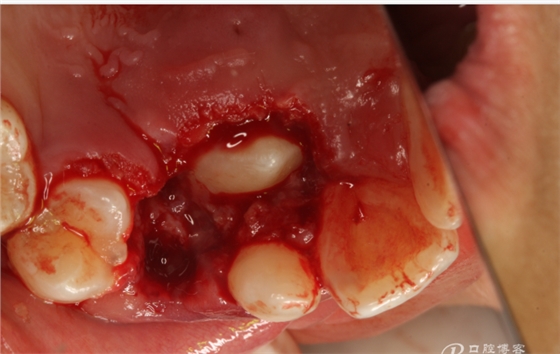

圖11.從乳尖牙到13牙冠區(qū)域去皮質(zhì)骨化處理